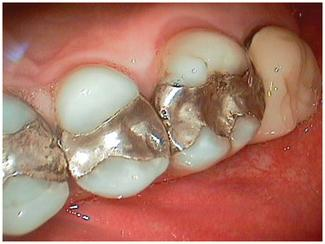

For instance, many patients, when given the option, may prefer to combine both immediate-need treatment with future-need treatment. Advantages of this approach include decreased chair time and fewer visits, impressions, and injections (Fig 4). From a restorative standpoint, we can often better manage the occlusion and blending of restorative materials for an optimal result when the dentistry is approached in a more integrated way.

For patients to proceed with treatment in a comprehensive way, they must feel confident in our ability to deliver care. There are multiple methods of demonstrating capability to patients — clean and tidy offices, pleasant, long-term staff members, and patient testimonials. However, I have found that sharing photographs of restored arches that demonstrate the transformations possible with modern materials and techniques is very effective (Figs. 5 and 6; 7 and 8). Just as everyone appreciates how restorative dentistry can improve a person’s smile, patients also appreciate how posterior dentistry can improve a deteriorating situation — especially when the preoperative case reflects their own needs.